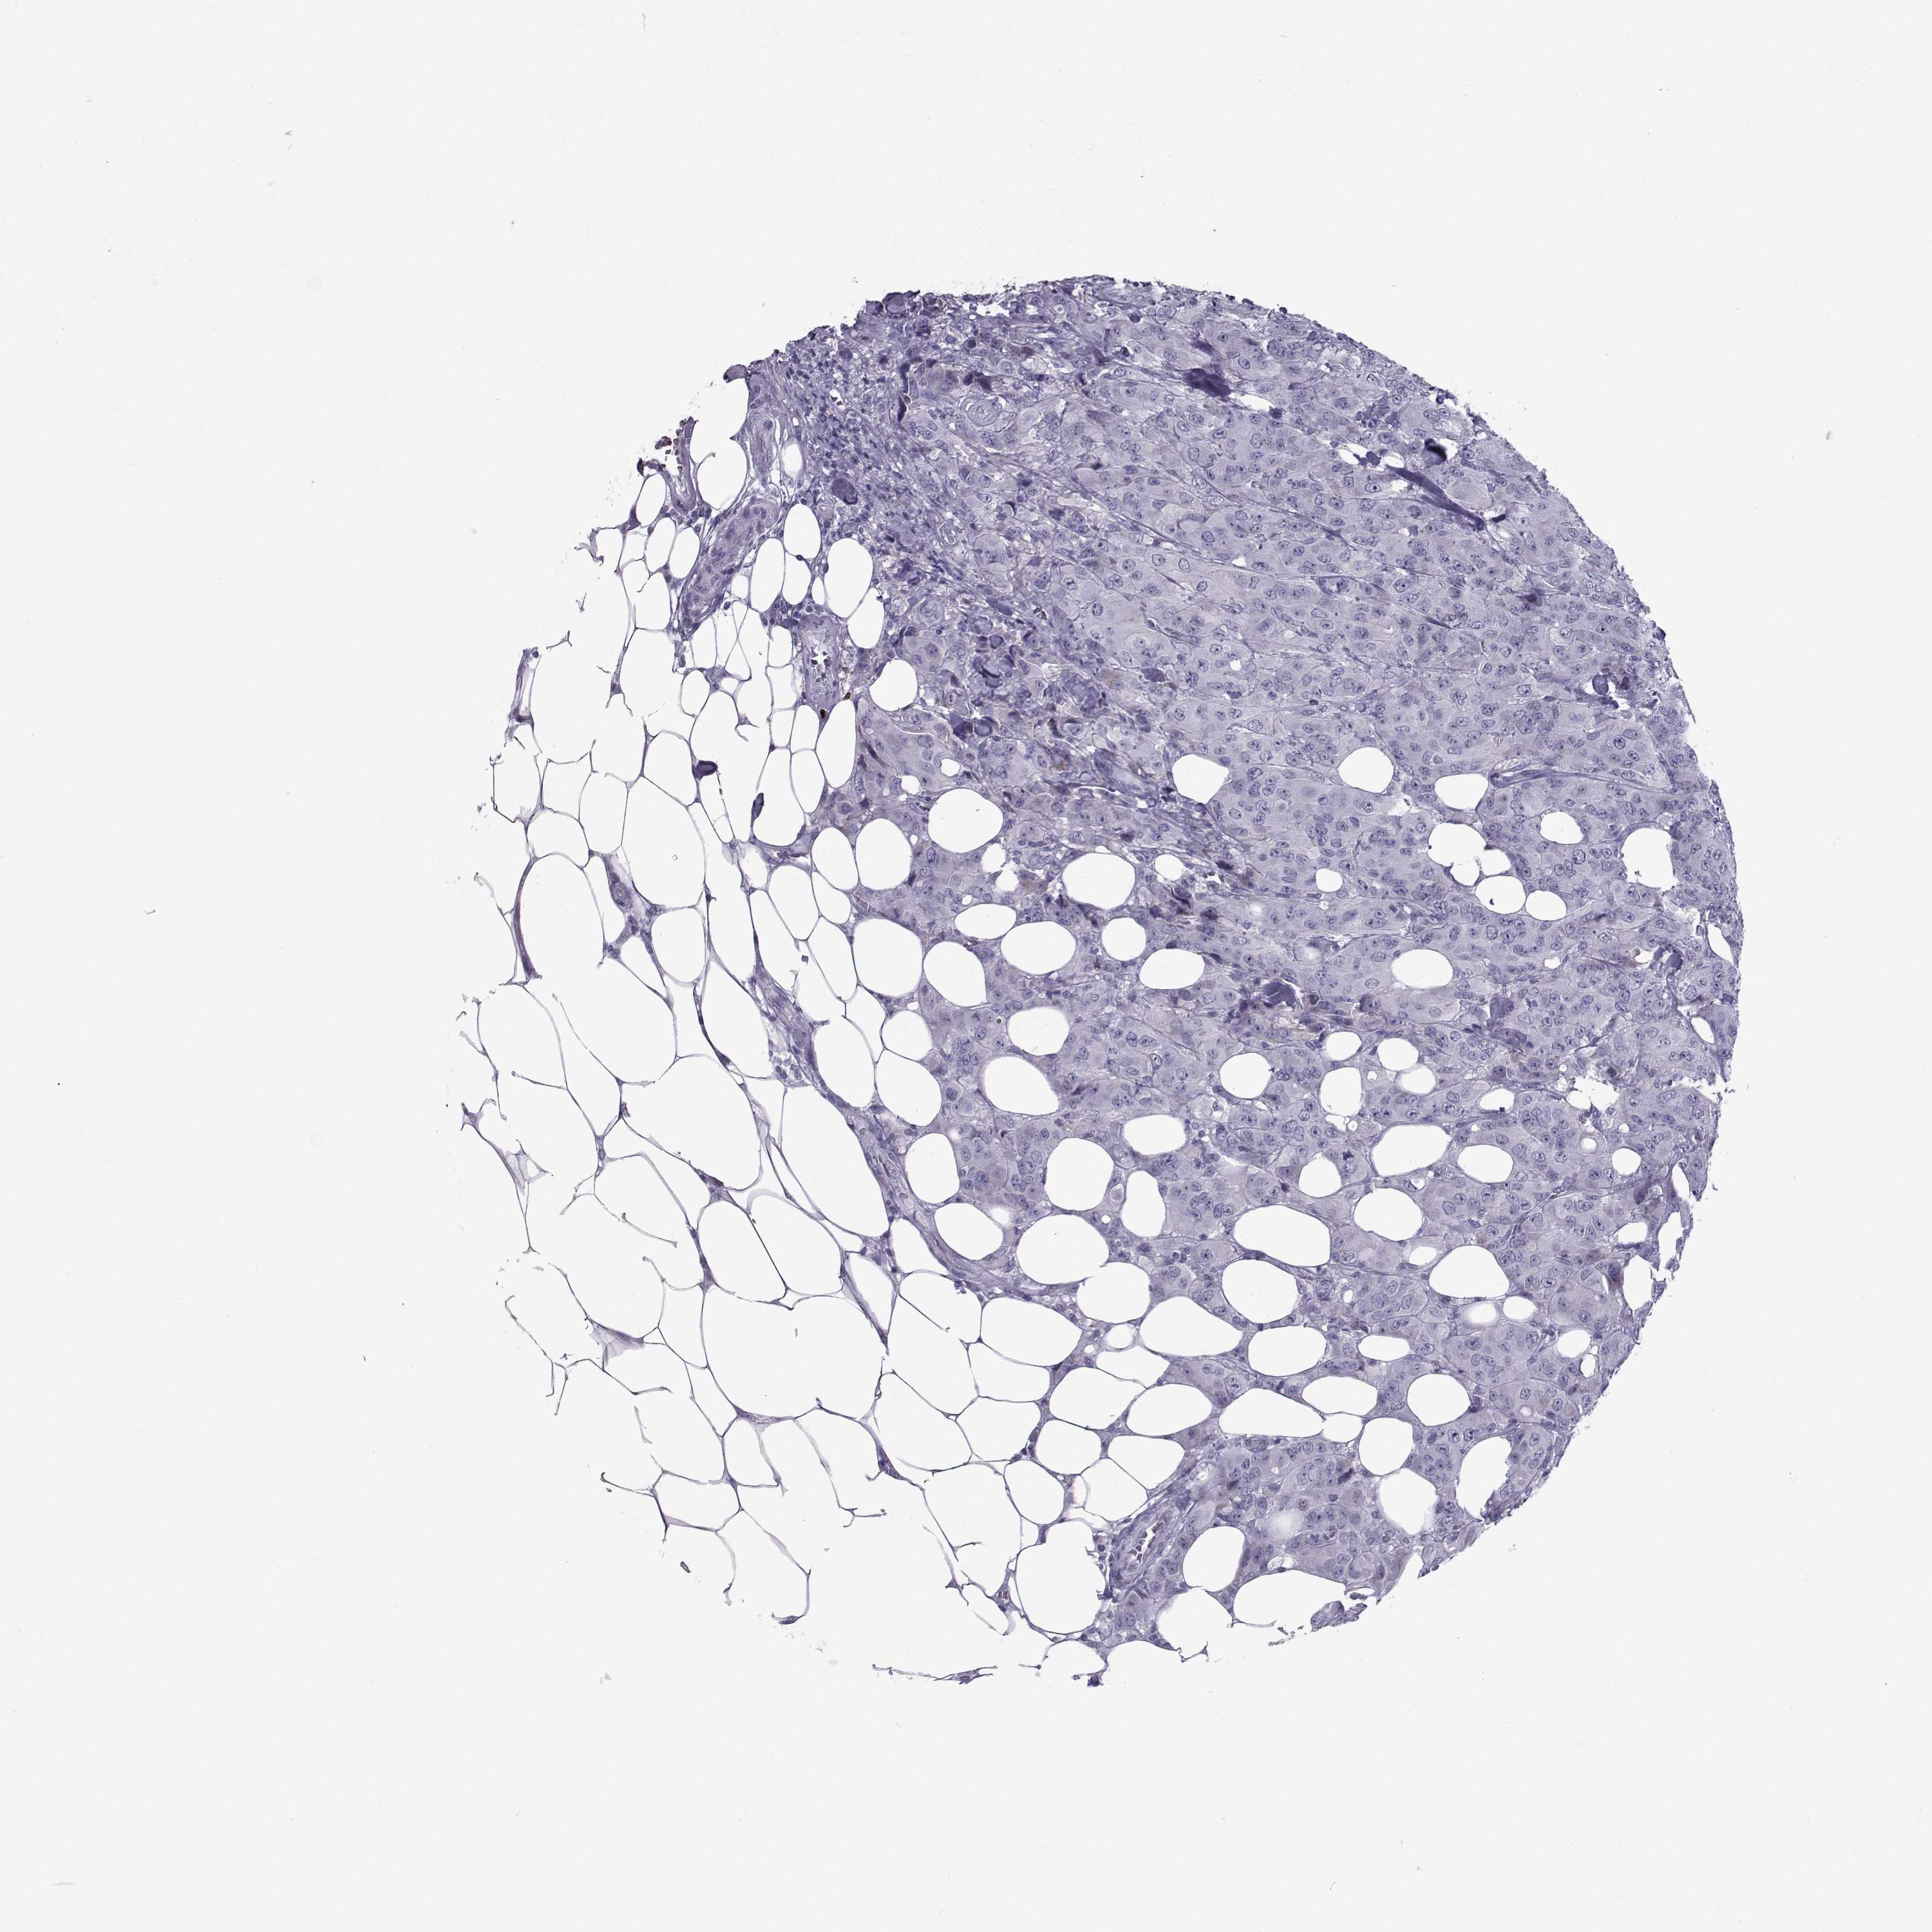

Breast cancer

Human cancer